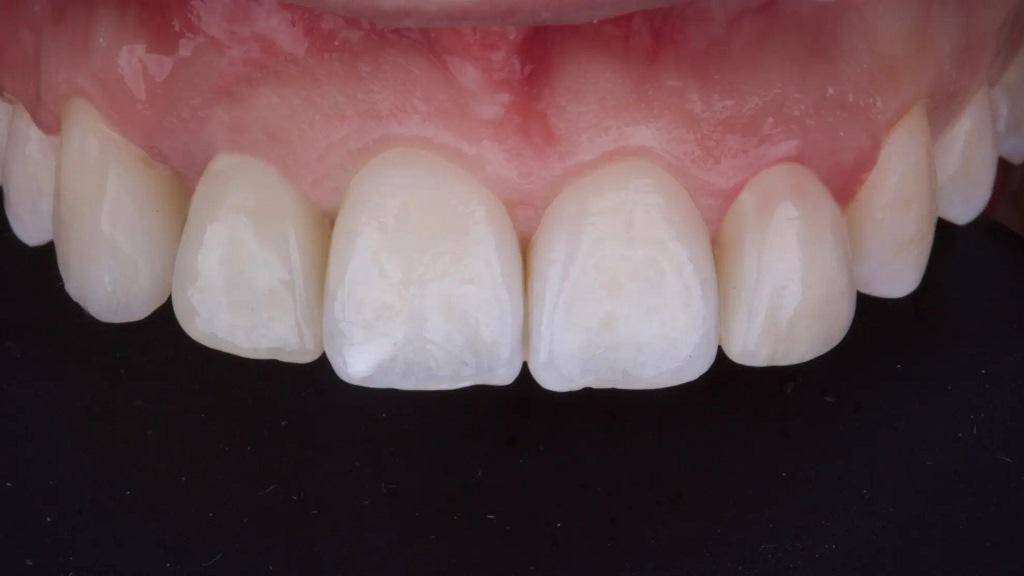

После четырех месяцев заживления была проведена малоинвазивная процедура вскрытия и сделан цифровой слепок. Через две недели для придания контура мягким тканям вокруг имплантата была установлена временная реставрация с винтовой фиксацией (фото 7-8).

Фото 7: Заживление тканей после установки имплантата и пересадки соединительной ткани.

Фото 8: Временная винтовая реставрация устанавливается для придания формы мягким тканям вокруг имплантата.